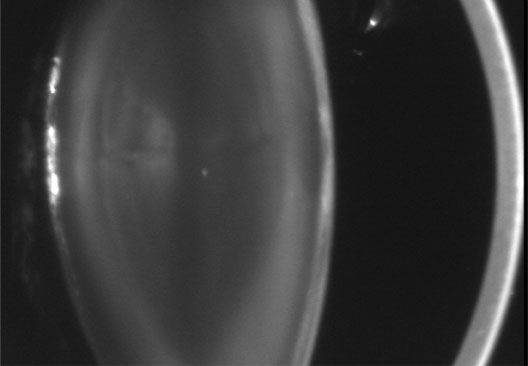

The dense bilateral lens opacities may present as a biconvex-shaped cataract or as posterior, polar, nuclear, or total cataract. The discoid lens shape may result from loss of lens material due to a posterior lens capsule defect4 or defective lens fiber formation and subsequent degeneration.5 The cataracts are present at birth, and glaucoma may be present congenitally or develop within the first 3 years of life. Other ocular findings may include corneal opacity, mitotic pupil, enophthalmos, and hypotonia.6 The cognitive impairment presents with a discrete behavioral phenotype that includes temper tantrums, irritability, complex repetitive behaviors, and unusual mannerisms. Severe renal Fanconi's syndrome may lead to progressive renal impairment. Most boys will develop a distinctive facies and habitus, and attain a height of less than 5 feet because of developmental retardation. Female carriers manifest characteristic but usually asymptomatic lenticular opacities that will correctly identify carrier status with 100% sensitivity in postpubertal females. These opacities are typically small, irregularly shaped, off-white or gray in color, nonrefractile in appearance, and distributed around the lens equator, more anteriorly than posteriorly (Figs. 1 and 2). Most importantly, and distinctively, these opacities are clustered in radial bands or wedges in the peripheral cortex of the lens and are visible by retroillumination. Typically, the opacities are moderately dense for one or two clock-hours, are then less numerous or even absent for another clock-hour or two, and so on. These opacities must be differentiated from the polychromatic, iridescent “crystals” found in Steinert's myotonic dystrophy (DM), gray-white random opacities in carriers of X-linked adrenoleukodystrophy, sutural opacities in Nance-Horan's (NH) syndrome, snowflake granules beneath the anterior and posterior capsule in diabetes mellitus, highly uniform white dots of hypoparathyroidism, and equatorial opacities in cataracta coronaria or ceruleana. Some females also manifest a dense white, central, posterior cortical cataract in the precapsular area. Although the posterior central cataract is apparently congenital, the equatorial and anterior cortical punctate opacities are uncommon in prepubertal female Lowe's syndrome carriers.7 Carrier status may also be confirmed by DNA diagnosis.

Fig. 1. OCRL. Female carrier with typical small, irregularly shaped, off-white or gray, nonrefractile opacities in the anterior lens cortex, slit-lamp view. (Courtesy of Dr. R.A. Lewis, Baylor College, Houston, Texas.)